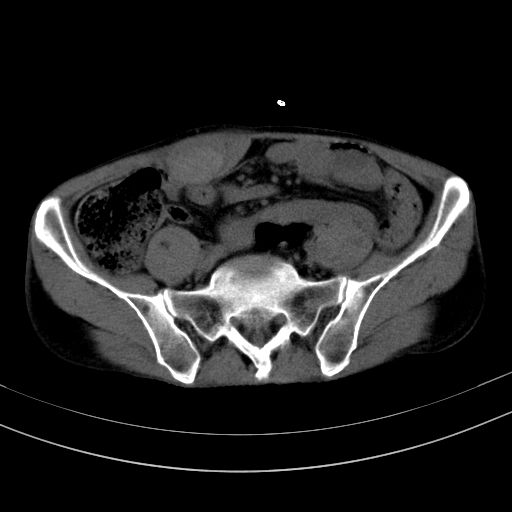

以下是引用37度在2010-1-9 14:37:00的发言:[br]1.双肾囊肿,左肾积水结石,.胆总管轻度扩张;[br]2.病灶在腹膜外,考虑纤维瘤。

以下是引用dyqct在2010-1-9 17:56:00的发言:[br]考虑:1.双肾囊肿,左肾积水结石、旋转不良。[br] 2.右侧腹直肌血肿或纤维瘤。[br]肠道准备不好。做个增强。